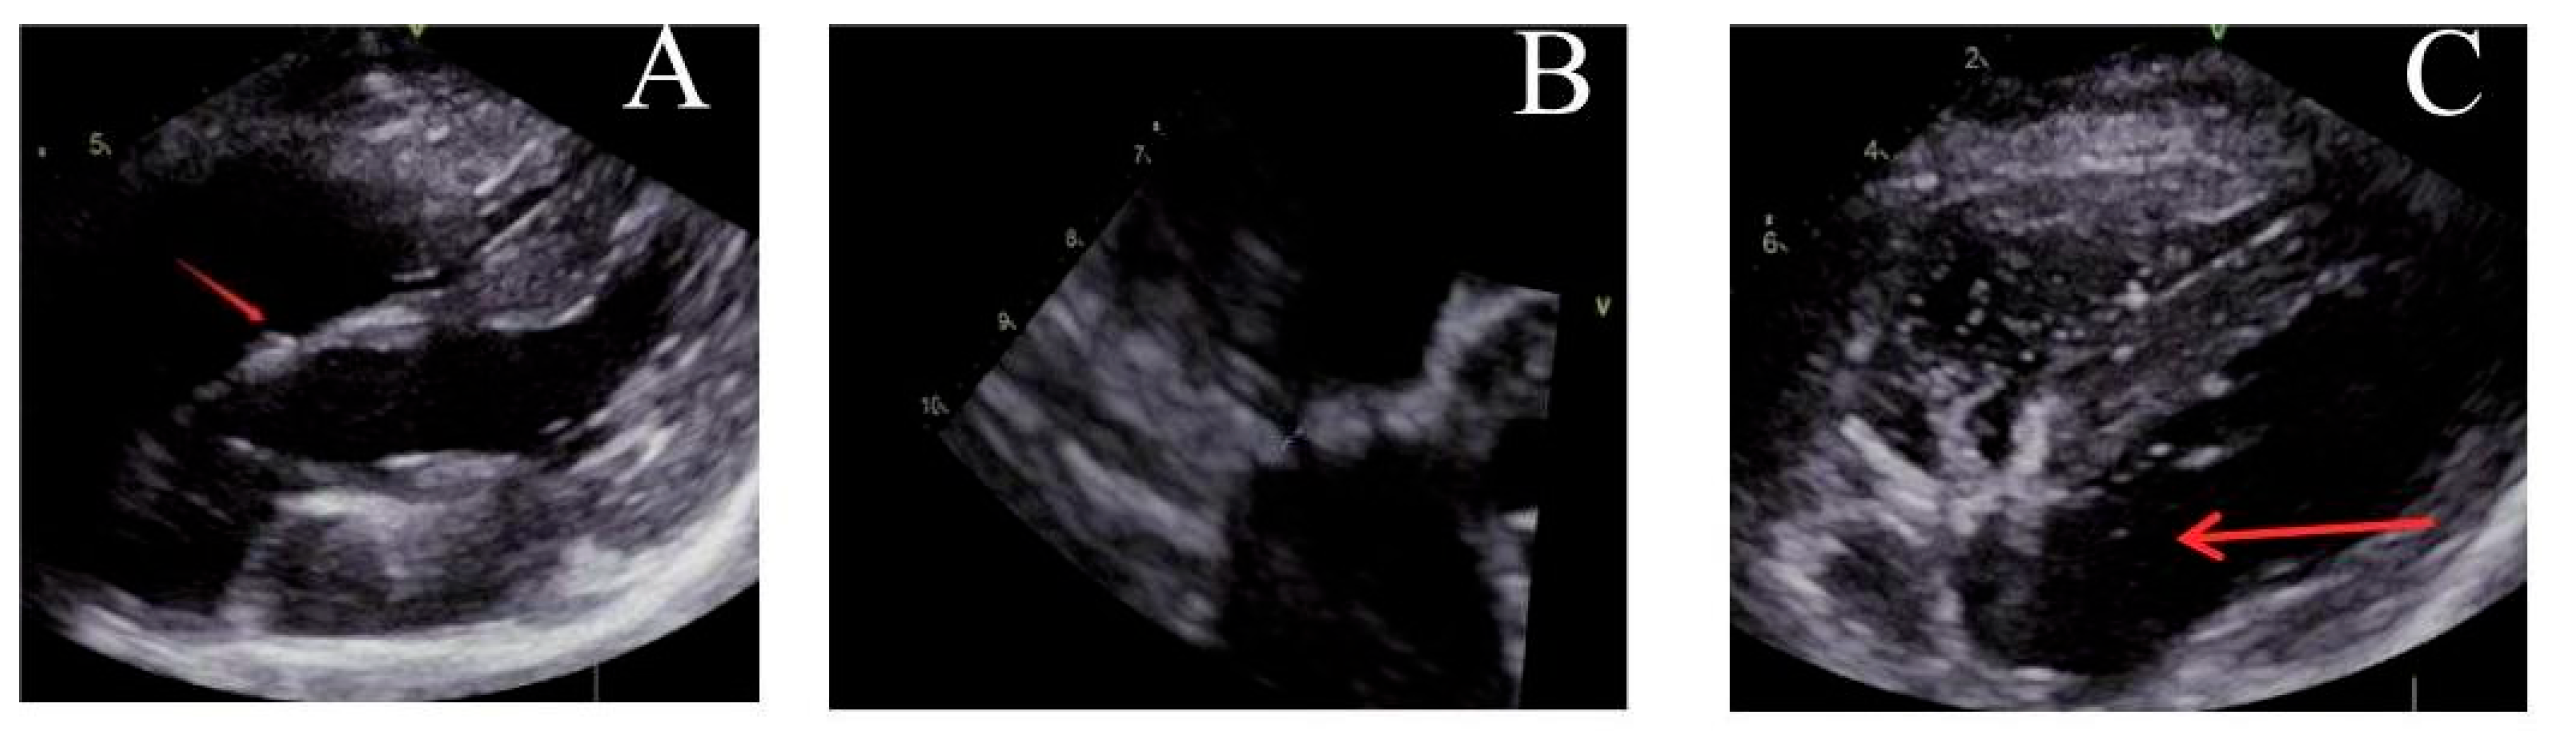

Post-implantation, the locking mechanism remained stable without suture breakage, thrombus formation, or neoplastic changes. The locking device was clearly visualized on ultrasound. Both the atrial septal defect diameter and residual shunt flow velocity decreased significantly over time, with near-complete defect closure observed by 6 months (postoperative ultrasound at immediate, 1, 3 and 6 months respectively, Fig. 3, Fig. 4, Fig. 5 and Fig. 6). Left ventricular hemodynamics and function remained unaffected.

Figure 3: Immediate postoperative ultrasound observation. (A) The locking node is intact, (B) the size of the atrial septal defect is significantly reduced, and (C) there are a few bubbles in the left atrium.

Figure 4: Ultrasound observation one month after operation. (A) The locking node is intact, (B) the size of the atrial septal defect further decreases, and (C) there are trace bubbles in the left atrium.